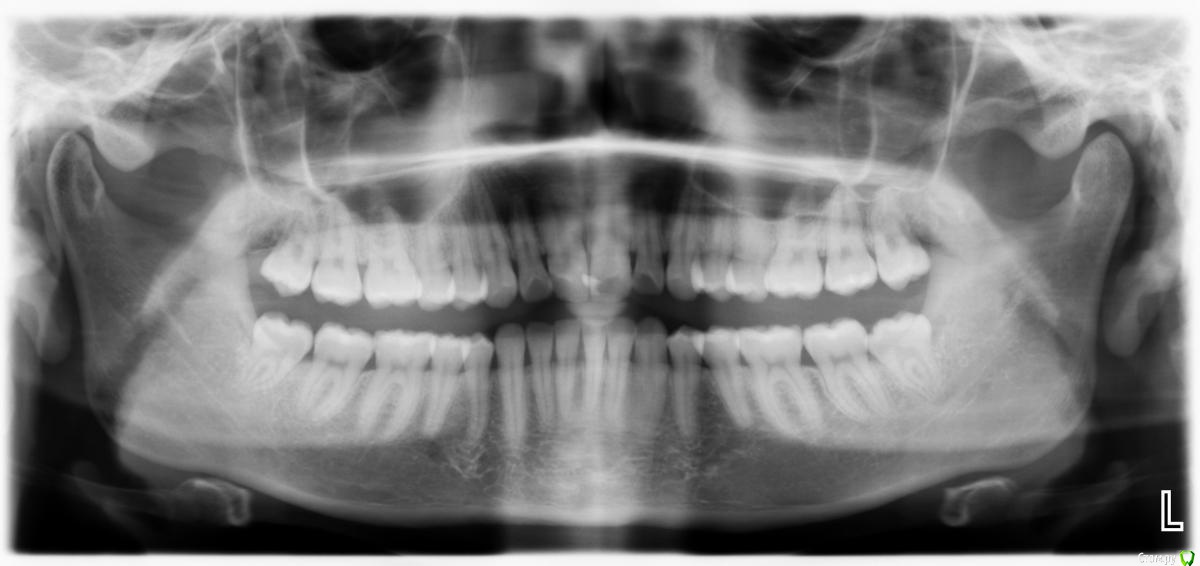

Ситуация следующая: сколько себя помню, всегда на зубах были белые пятна. Сейчас белые пятна почти на всех зубах и местами коричневые. Я не помню, когда появились коричневые пятна и очень беспокоюсь, что состояние эмали может в дальнейшем ухудшиться.

Врачи, у которых я консультировалась ставят разные диагнозы: флюороз, гипоплазия эмали. Рекомендуют наблюдаться и, к сожалению, не могут дать никаких прогнозов о развитии заболевания.

Фото зубов и снимок прилагаю. Буду очень благодарна за ваше профессиональное мнение.

Это у вас гипоплазия эмали вследствии флюороза, или так называемые крапчатые зубы. Что делать?, Ничего страшног просто участки с поврежденной эмалью очень хрупкие и поэтому выкрашиваются, просто пломбируйте, зато у вас устойчивостьт к кариесу повышенная

Крошатся всмысле участки эмали разрушаются,открывая дентин который под эмалью, он сам по себе темнее и активно окрашивается, поэтому нада реставрировать утраченные участки эмали,фторирование вам не требуется,

Крошиться будут и дальше. Нужно следить и пломбировать вовремя.  Неприятно, но не страшно)